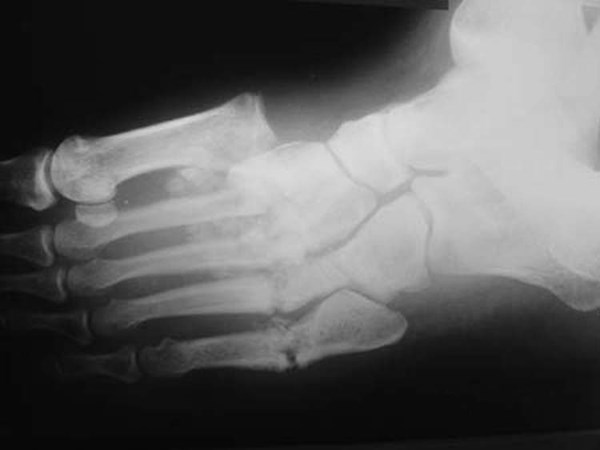

• Serial plain X-rays of the foot:  all non-superficial diabetic foot infections should be assessed with serial plain X-rays with intervals of 2 weeks or more between X-rays to identify bone abnormalities (e.g., deformity, destruction) as well as soft tissue gas and radiopaque foreign bodies [70][72].

• Radiographs tangential to the bone surface at the site of suspected bone infection are ideal to visualize a potential focus of osteomyelitis, in addition to the standard radiographs of the region. Single plain X-rays have low sensitivity and specificity for diagnosis osteomyelitis but serial plain X-rays obtained with an interval of at least 2 weeks are more likely to predict the presence of osteomyelitis [70]. The classical radiologic sign of osteomyelitis is focal loss of bone density, almost always adjacent to the ulcer bed (Figure 13) [40]. Characteristic features of osteomyelitis on plain X-rays of the foot are summarized in Table 6.

Figure 13. Osteomyelitis of the first metatarsophalangeal joint [111]